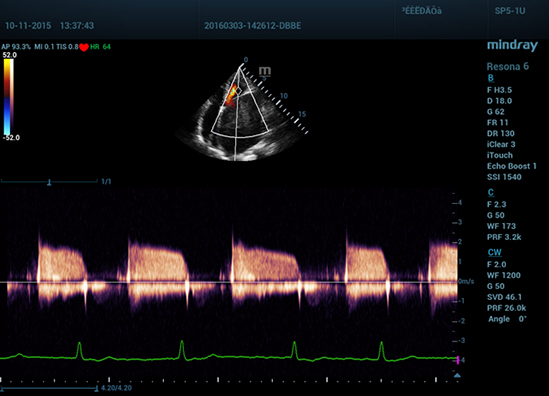

–Ю–±–µ—Б–њ–µ—З–Є–≤–∞—П –Ї–∞—З–µ—Б—В–≤–Њ –Є–Ј–Њ–±—А–∞–ґ–µ–љ–Є—П —Г—А–Њ–≤–љ—П –њ—А–µ–Љ–Є—Г–Љ, Resona 6 —В–∞–Ї–ґ–µ –њ–Њ–≤—Л—И–∞–µ—В –Ї–ї–Є–љ–Є—З–µ—Б–Ї–Є–µ –≤–Њ–Ј–Љ–Њ–ґ–љ–Њ—Б—В–Є –Є—Б—Б–ї–µ–і–Њ–≤–∞–љ–Є—П –њ—А–Є –њ–Њ–Љ–Њ—Й–Є —А–µ–≤–Њ–ї—О—Ж–Є–Њ–љ–љ–Њ–є —Б–Є—Б—В–µ–Љ—Л V Flow, –њ—А–µ–і–љ–∞–Ј–љ–∞—З–µ–љ–љ–Њ–є –і–ї—П –Њ—Ж–µ–љ–Ї–Є –≥–µ–Љ–Њ–і–Є–љ–∞–Љ–Є—З–µ—Б–Ї–Є—Е –њ–Њ–Ї–∞–Ј–∞—В–µ–ї–µ–є —Б–Њ—Б—Г–і–Њ–≤; –Њ–±–µ—Б–њ–µ—З–Є–≤–∞–µ—В –Є–љ—В–µ–ї–ї–µ–Ї—В—Г–∞–ї—М–љ–Њ–µ –њ–Њ–ї—Г—З–µ–љ–Є–µ –Є–Ј 3D –і–∞–љ–љ—Л—Е –љ–∞–Є–±–Њ–ї–µ–µ –≤–∞–ґ–љ—Л—Е –њ—А–Њ–µ–Ї—Ж–Є–є –і–ї—П –і–Є–∞–≥–љ–Њ—Б—В–Є–Ї–Є –¶–Э–° –њ–ї–Њ–і–∞. –°–Њ—З–µ—В–∞—П –≤ —Б–µ–±–µ –Є–љ—В—Г–Є—В–Є–≤–љ–Њ –њ–Њ–љ—П—В–љ–Њ–µ —Б–µ–љ—Б–Њ—А–љ–Њ–µ —Г–њ—А–∞–≤–ї–µ–љ–Є–µ —Б —А–∞—Б–њ–Њ–Ј–љ–∞–≤–∞–љ–Є–µ–Љ –ґ–µ—Б—В–Њ–≤ –Є –≤—Б–µ –≤–∞–ґ–љ—Л–µ –Ї–ї–Є–љ–Є—З–µ—Б–Ї–Є–µ —Е–∞—А–∞–Ї—В–µ—А–Є—Б—В–Є–Ї–Є, –њ–µ—А–µ–і–Њ–≤–∞—П —Б–Є—Б—В–µ–Љ–∞ Resona 6 –љ–∞—Б—В–Њ—П—Й–∞—П –љ–Њ–≤–∞—П –≤–Њ–ї–љ–∞ –≤ —Б—Д–µ—А–µ —Г–ї—М—В—А–∞–Ј–≤—Г–Ї–Њ–≤—Л—Е –Є–љ–љ–Њ–≤–∞—Ж–Є–є.

UWN+?(–љ–µ–ї–Є–љ–µ–є–љ–∞—П –≤–Є–Ј—Г–∞–ї–Є–Ј–∞—Ж–Є—П –≤ —Г–ї—М—В—А–∞—И–Є—А–Њ–Ї–Њ–Љ –і–Є–∞–њ–∞–Ј–Њ–љ–µ) –і–ї—П –Ї–Њ–љ—В—А–∞—Б—В–љ–Њ–є —Н—Е–Њ–≥—А–∞—Д–Є–Є –њ–Њ–Ј–≤–Њ–ї—П–µ—В —Б–Є—Б—В–µ–Љ–µ Resona 6 –Њ–±–љ–∞—А—Г–ґ–Є–≤–∞—В—М –Є –Є—Б–њ–Њ–ї—М–Ј–Њ–≤–∞—В—М –Ї–∞–Ї –≤—В–Њ—А—Л–µ –≥–∞—А–Љ–Њ–љ–Є–Ї–Є, —В–∞–Ї –Є –љ–µ–ї–Є–љ–µ–є–љ—Л–µ –њ–µ—А–≤–Є—З–љ—Л–µ —Б–Є–≥–љ–∞–ї—Л. –Ґ–µ—Е–љ–Њ–ї–Њ–≥–Є—П –њ–Њ–Ј–≤–Њ–ї—П–µ—В —Б–Њ–Ј–і–∞–≤–∞—В—М –Є–Ј–Њ–±—А–∞–ґ–µ–љ–Є—П –Ї–Њ–љ—В—А–∞—Б—В–љ–Њ–є —Н—Е–Њ–≥—А–∞—Д–Є–Є –±–Њ–ї–µ–µ –≤—Л—Б–Њ–Ї–Њ–≥–Њ –Ї–∞—З–µ—Б—В–≤–∞ —Б –±–Њ–ї—М—И–µ–є —З—Г–≤—Б—В–≤–Є—В–µ–ї—М–љ–Њ—Б—В—М—О –Ї–Њ –≤—В–Њ—А–Њ—Б—В–µ–њ–µ–љ–љ—Л–Љ —Б–Є–≥–љ–∞–ї–∞–Љ, –±–Њ–ї—М—И–Є–Љ –≤—А–µ–Љ–µ–љ–µ–Љ –і–µ–є—Б—В–≤–Є—П –∞–Ї—В–Є–≤–љ–Њ–≥–Њ –≤–µ—Й–µ—Б—В–≤–∞ –Є –±–Њ–ї–µ–µ –љ–Є–Ј–Ї–Є–Љ–Є —В—А–µ–±–Њ–≤–∞–љ–Є—П–Љ–Є –Ї –Є–љ—В–µ—А–≤–∞–ї—Г –Є–Ј–Љ–µ—А–µ–љ–Є—П.